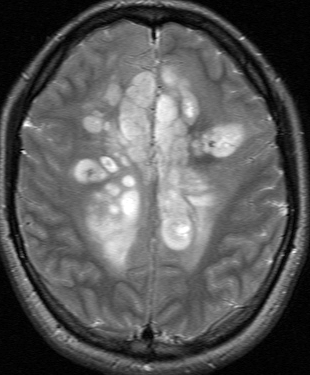

若い成人です,認知機能障害で発症しました。この画像を見るからに悪性神経膠腫,少なくともグレード3のグリオーマであることは明白です。しかし,グレード4膠芽腫あるいはグレード3退形成性星細胞腫にしては腫瘍周辺浮腫が軽すぎます。ですから,グレード3の退形成性乏突起膠腫 AO かも。認知機能の回復と温存を考量して,脳梁損傷と前交連損傷を避けて,右上前頭回と帯状回腫瘍を摘出しました。

左は術後のT1強調ガドリニウム増強像で,残存腫瘍がわかります。この腫瘍に対してICE (IFO/CDDP/VP-16) 化学療法を1コースしました。右側のMRIが1ヶ月後の画像です。このように1p/19q欠失のある退形成性乏突起膠腫は,化学療法感受性がとても高い悪性グリオーマです。ですから,手術で後遺症を残さないように,勢い込んで腫瘍を摘出しようとしないことが大切です。光顕診断はAOで,後々の解析で1p/19q codeletion でした。